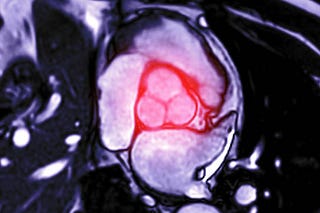

Valva mitral e o risco de morte súbita

O que o Prolapso da Valva Mitral e a Disjunção do Anel Mitral têm a ver com arritmias?